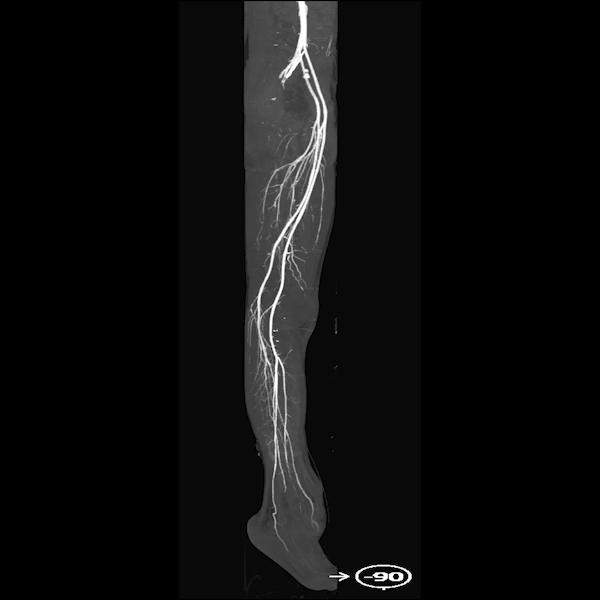

Additionally, a Maximum Intensity Projection (MIP) of the lower extremities was performed to assess blood flow through the arteries and detect any narrowing or vascular obstructions. The 3D Lab employed extensive segmentation efforts to enable clear MIP visualization without interference from bones or other dense structures. This was a significant technical challenge due to the proximity of vessel and bone pixels in the dataset and the presence of hematomas, where automated tools typically fall short, especially in trauma cases.

Figure C: The MIP clearly shows the lower extremity arteries on both sides, with no significant stenosis or obstructions, offering a clear view of blood flow from the pelvis to the legs.